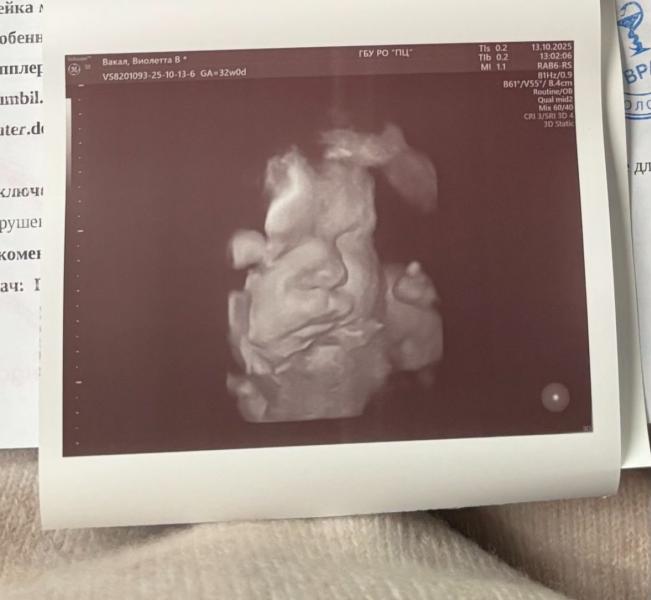

Какой характер будет у ребенка, если похож на папу?

А недовольные мы в папу😄

Интересно, какой характер у нее